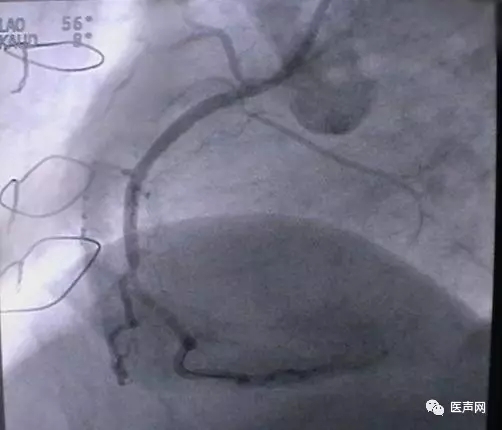

病例4:LAD PCI术后,对角支远端病变

此病变上次PCI不成功,因为LAD有支架,导丝穿过支架网眼入对角支有困难(对角支发出角度很大,成直角(箭头所示)。此次不再尝试,要学会放弃。

见下图: